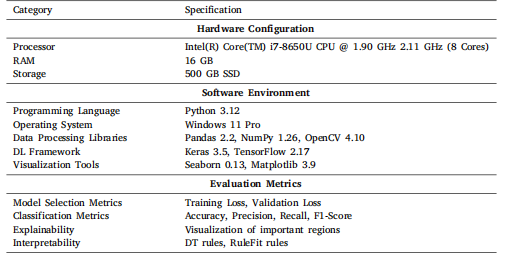

This section introduces information about the experiments performed and the results produced in this study. This section also prvides additional information about the datasets, experimental setup,optimized hyper-parameters, and evaluation metrics used in this study.

本节介绍本研究中开展的实验及其产生的结果,还提供了关于本研究中使用的数据集、实验设置、优化的超参数和评估指标的额外信息。

Table 4Experimental setup: Software and hardware specifications

表4 实验设置:软件和硬件规格。